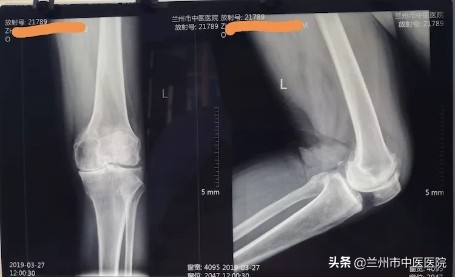

入院症见:左膝关节肿胀、疼痛,屈伸活动受限,上下楼梯困难,不能下蹲,行走困难睡眠差,食纳可,二便调。查体:左膝关节肿胀,屈伸活动受限,内侧间隙压痛(+),股骨内上髁压痛(+),髌尖粗面压痛(+),浮髌试验(-),髌骨研磨试验(+),入院后查左膝关节正侧位片及腰椎正侧位片如下:

风湿科李主任认真查体、阅片后提出:膝关节骨性关节炎临床上将其分为四期,该患者以左膝关节内侧间室退变为主,内侧间隙明显变窄,内侧半月板基本消失,关节面硬化,关节功能部分障碍,符合三期改变,患者曾就诊于多家医院,均建议手术治疗,由于患者经济能力及针对手术的恐惧心理,拒绝手术治疗。后经朋友介绍,张某就诊于我科,根据软组织外科学查体发现,患者腰骶部存在广泛压痛,尤以左侧腰部深层肌、腰背筋膜、髂胫束、臀上皮神经、髂后上棘、臀中肌、股骨内上髁、膝关节内侧间隙以及髌尖粗面压痛为甚。综合分析,该患者最早以椎管外腰骶部软组织损伤为主,其无菌性炎症反应产生剧烈的腰部疼痛症状,进一步引起腰骶部、臀部及大腿内侧肌群痉挛,继而出现“因痛增痉(挛)”和“因痉(挛)增痛”的恶性循环,久而久之,导致患者出现脊柱侧弯、椎体旋转、骨盆失稳。膝关节是人体负重关节,承受着人体的自身重量,腰骶椎及骨盆失稳会导致下肢力线发生改变,最终导致患者左膝关节受力集中于内侧,进一步加重了左膝内侧半月板磨损以至基本消失,如下图所示: